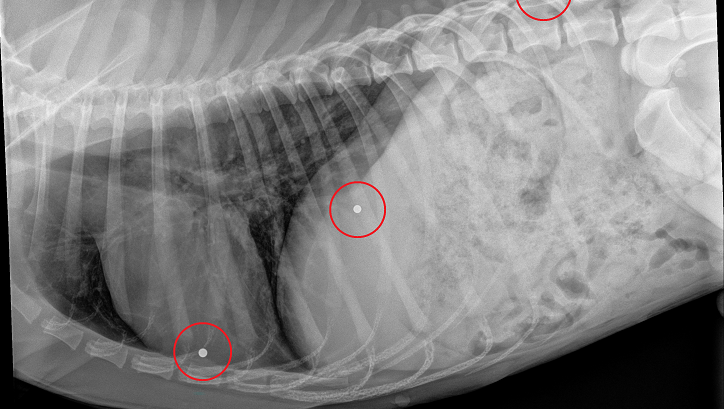

A Note from Wagster’s Foster Family: We don’t know what all happened to Wagster before the night he was found on Hwy 90, but we know it has not been an easy life. Along with his injuries from being hit by a car, X-rays revealed he had been shot multiple times with a BB gun. He also has several puncture wounds, so it appears he was in a dog fight before being hit by a car. He has heartworms, and we have started treatment. He started coughing the first night home, so he likely contracted kennel cough. On top of all of this, Wagster was whipped around so hard when he was hit that he can’t hear. Nobody knew he couldn’t hear because he engages with people so well. UPDATE Oct 6: His hearing is starting to come back! Hopefully, all of it will. Despite all he has been through, he is very sweet to everyone that he has encountered. He has not growled at all and waggles his tail at everyone he sees. UPDATE Oct 9: At first, Animal Control thought he was about seven years old because of the tartar build-up on his teeth, but with good nutrition and rest, his teeth look incredibly cleaner, so now they think he may be four or five years old.

Wagster is severely underweight AND had been shot multiple times. The veterinarian counted at least 5 BBs in him.

Wagster has a broken pelvic and broken femur (at the ball that goes into the hip). The ball at the top of the thighbone (femur) is called the femoral head.